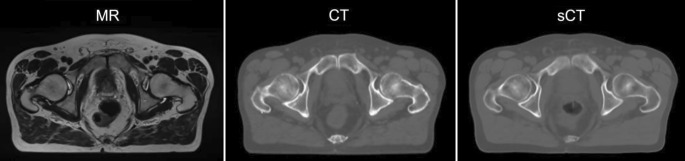

Fig. 5.

Synthetic computed tomography (sCT) calculated from magnetic resonance (MR) image only, using neural networks. This sCT can be used for radiation dose calculation just like an actual CT, which can in turn be skipped. (Courtesy of Lukas Fetty, Dept. of Radiotherapy, Medical University of Vienna)

In contrast to brachytherapy, where MR guidance can be considered as almost standard of care for treating cervical cancer [25], there is no consensus on how MRI is ideally integrated and adopted for external beam radiotherapy (EBRT). Since imaging in EBRT is used not only for defining targets and OAR but also for extracting attenuation information for dose calculation, some challenges need to be overcome when aiming at MRI-only-based EBRT, which would no longer need any planning CT scans (Fig. 5; [26–28]).